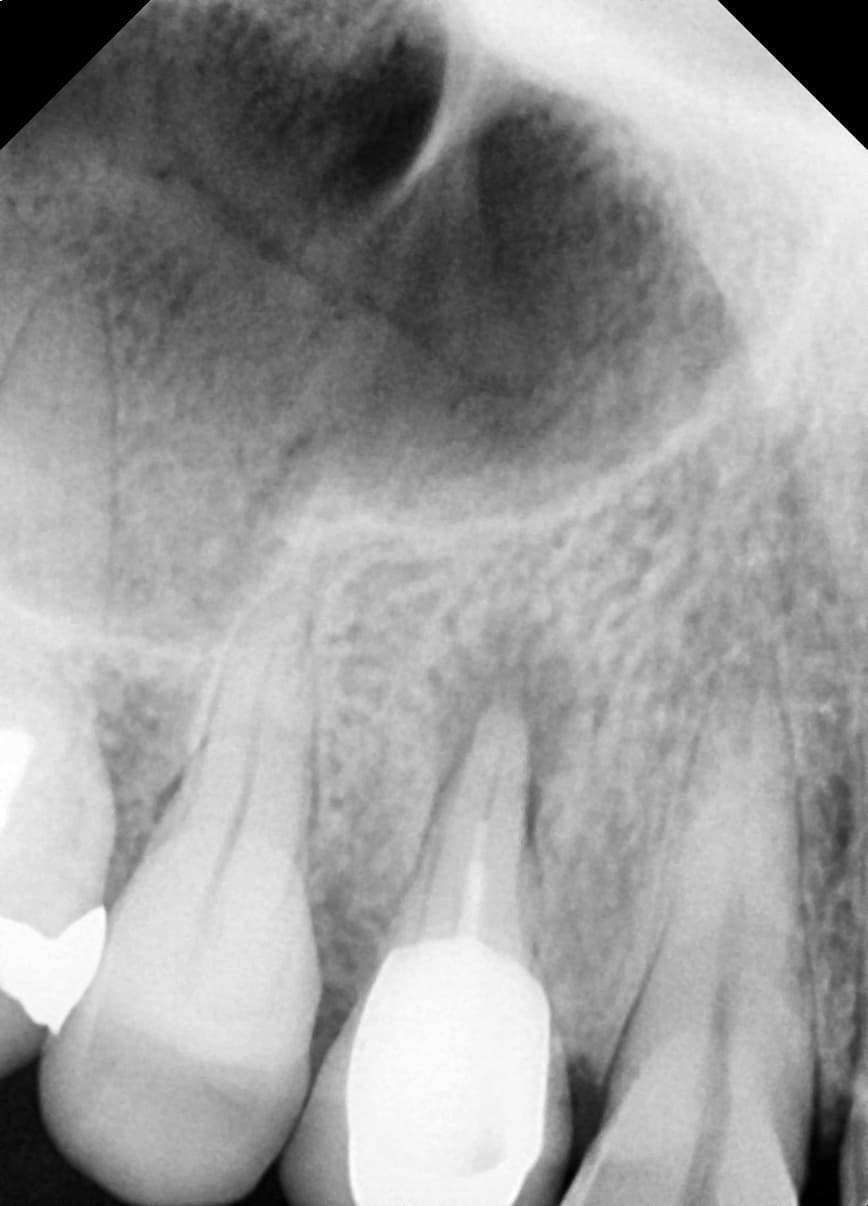

치근단병소 치유

뿌리 끝 염증으로 발치 권유받은 어금니

Before

After

신경치료 1년 2개월 후 치근단병소 완전 치유